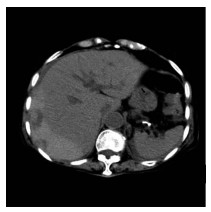

肝病超声诊断指南

中华医学会超声医学分会, 中国研究型医院学会肿瘤介入专业委员会, 国家卫生和健康委员会能力建设和继续教育中心超声医学专家委员会

2021, 37(8): 1770-1785. DOI: 10.3969/j.issn.1001-5256.2021.08.007

超声检查无创、实时、价廉,无辐射、便于反复进行,是最常用的肝脏影像学检查方法。近年来,超声检查新技术如超声造影、弹性成像发展迅速,可有效鉴别肝内占位性病变性质、评估肝纤维化和门静脉高压程度以及监测肝病治疗效果,在临床肝病及其介入治疗中发挥重要诊断价值。本指南规范了肝病多模态超声技术(灰阶超声、彩色多普勒超声、超声造影、弹性超声)检查的仪器调置、患者准备及医生检查方法;对肝脏弥漫性病变(炎性病变、纤维化、硬化)、多种占位性病变及肝病介入操作的多模态超声技术诊断标准进行了定义和规范,同时推荐了超声监测周期及肝脏疾病超声诊断报告书写规范。